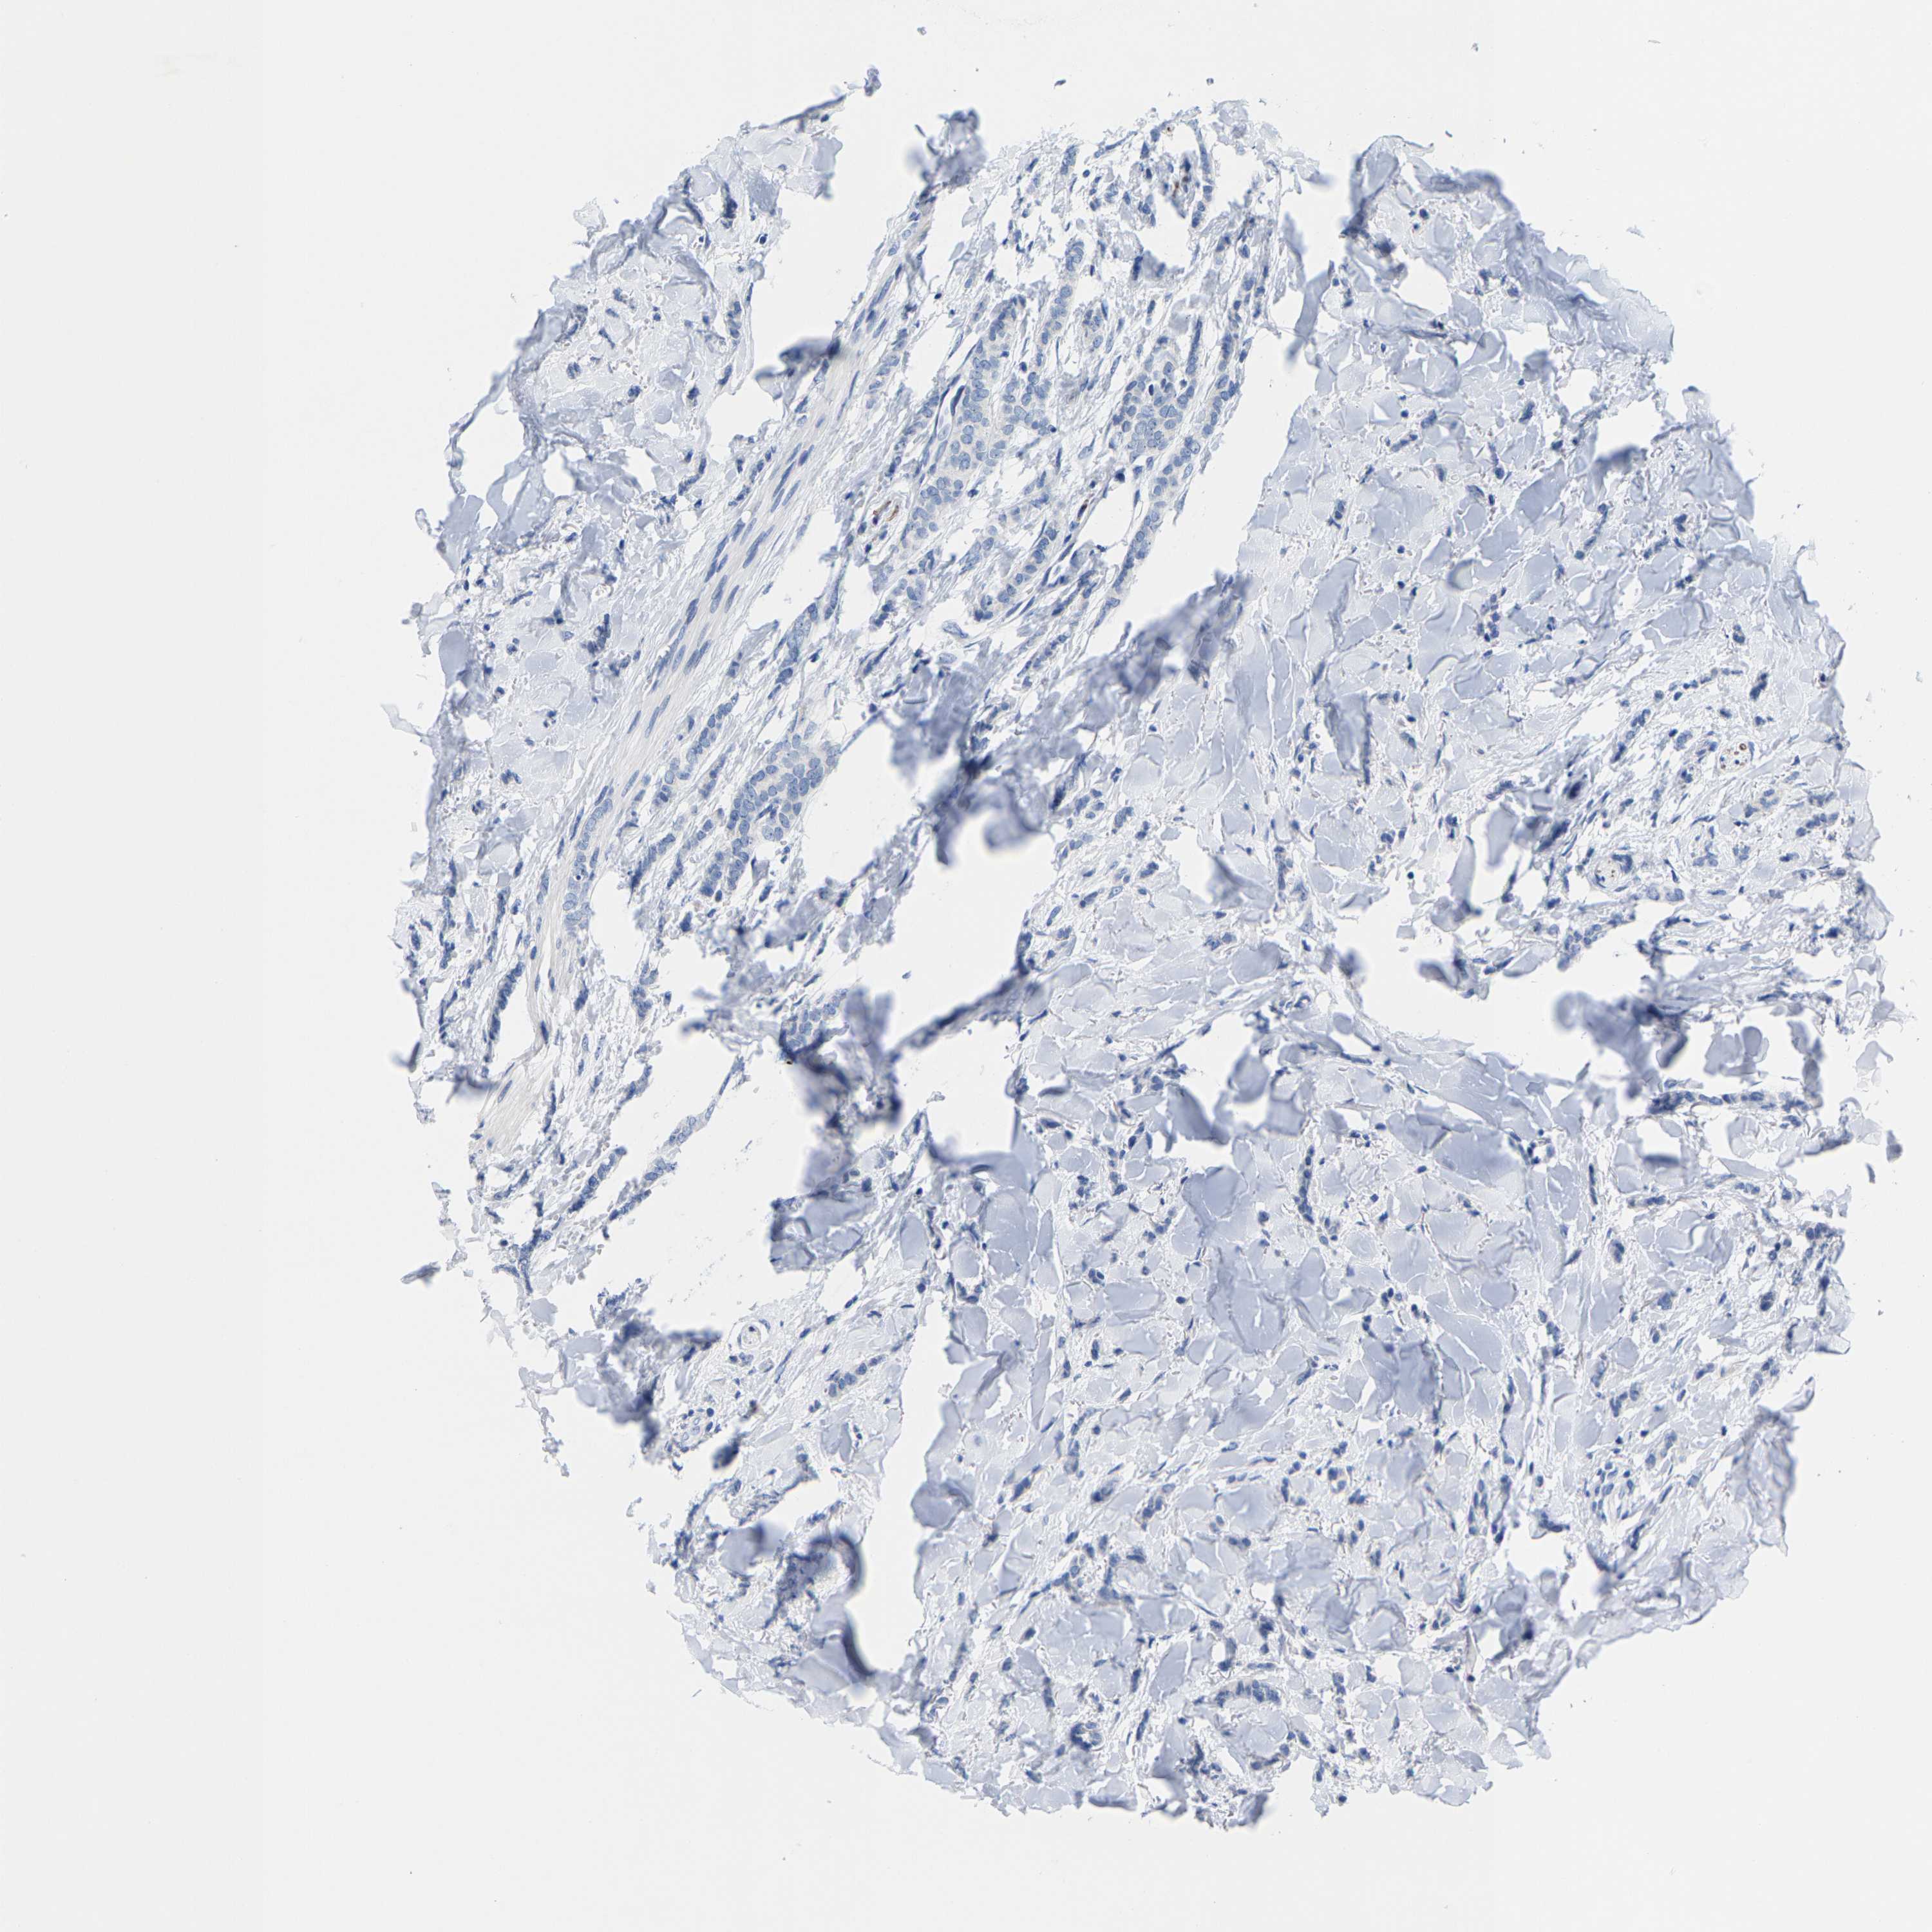

Breast cancer

Human cancer